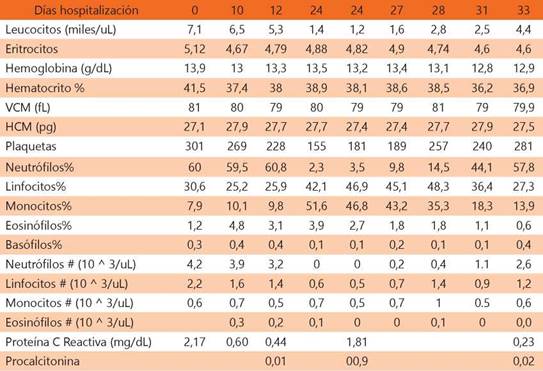

Masculino de 13 años de edad, niega antecedentes heredofamiliares, con antecedentes perinatales sin relevancia, niega alergias y hospitalizaciones, cuenta con antecedente de múltiples cuadros de otitis media supurativa desde los 5 años de edad, que se trataban de manera ambulatoria con antibióticos a base de penicilina e inihibidores de betalactamasas por vía oral, con remisión parcial del cuadro y recurrencia de la otorrea. Inicia su padecimiento actual 2 días previos a su ingreso con otorrea mucopurulenta fétida de oído derecho, de moderada a abundante acompañada de hipoacusia, el paciente niega tener fiebre o algún otro síntoma. A la exploración física se presenta neurológicamente íntegro, con otorrea mucopurulenta del conducto auditivo derecho, asi como aumento de volumen y temperatura de la región retroauricular derecha, la cual se observa hiperémica, reblandecida con dolor a la palpación. Prueba de Weber lateralizado a lado izquierdo. Se mantiene hemodinámicamente estable, los signos vitales dentro de niveles normales para la edad, sin datos de dificultad respiratoria. Es referido a un hospital de segundo nivel para iniciar tratamiento intravenoso. A su ingreso se realizan laboratorios de control los cuales muestran un hemograma normal, sin embargo, con Proteína C Reactiva (PCR) positiva (Ver tabla 1).

Tabla 1: Recuento de laboratorios durante la hospitalización. Se observa neutropenia absoluta al día 24 de tratamiento.

VCM: promedio del tamaño de glóbulos rojos; HCM: cantidad de hemoglobina por eritrocito

Durante su hospitalización se realiza Tomografía Axial Computarizada (TAC) de cráneo donde se reporta ocupación masteoidea derecha asociado a cambios líticos que condicionan pérdida de tabiques de celdillas mastoideas y comunicación con estructuras intracraneales (Ver figura 1). Se decidió iniciar tratamiento intravenoso a base de vancomicina a 60 mg/kg/día y piperacilina - tazobactam a 60 mg/kg cada 6 horas hasta su resolución quirúrgica, sin embargo, presentó pico febril aislado al día 24 de tratamiento, sin otras manifestaciones clínicas agregadas. Se realizó biometría hemática de control posterior al evento febril, donde se identificó leucopenia, con un recuento de neutrófilos de 0 x 10^3/uL, clasificándola como una neutropenia profunda, además se encontró una disminución del recuento plaquetario sin catalogarse como trombocitopenia. Dada su larga estancia intrahospitalaria sin otros antecedentes hematológicos se sospechó de neutropenia secundaria a fármacos, por lo que se utilizó la escala de Naranjo para identificar la posible causalidad entre los fármacos utilizados en el paciente, obteniendo una puntuación de 7 para vancomicina (probable)17. Para descartar la etiología autoinmunitaria se realizaron pruebas para anticuerpos anti-citoplasma de neutrófilos (ANCA) resultando negativos. El día 24 del uso de vancomicina se suspendió tratamiento y se continuó con un fármaco derivado de lincomicina (clindamicina). A las 72 horas del retiro del fármaco se realizó un control de laboratorios observando un incremento en el recuento de neutrófilos, con una recuperación total al día 9 de la suspensión del fármaco (Ver figura II). Es valorado por el servicio de otorrinolaringología (ORL) pediátrica, se decidió realizar una mastoidectomía radical amplia derecha con timpanoplastía, la cual se realizó sin complicaciones. El paciente presentó evolución favorable sin datos de parálisis facial con recuperación gradual de la hipoacusia. Se egresó con cita a la consulta externa de ORL donde actualmente se reporta sin secuelas.

El primer caso reportado en pacientes pediátricos se realizó en 1994 por Y. Todd y colaboradores, en un preescolar de 2 años con sospecha de endocarditis secundaria a un defecto del tabique interventricular, después de 18 días de tratamiento con vancomicina con un recuento mínimo de neutrófilos de 990 x 10^3/uL18, en comparación, nuestro paciente presentó una afección más marcada, documentándose una neutropenia absoluta de 0x10^3/uL, sin otras manifestaciones clínicas. Dintel y colaboradores reportaron afección a otras líneas celulares en un adulto, con una tríada inusual que desarrolló leucopenia, trombocitopenia y eosinofilia6, sin embargo nuestro caso mostró únicamente afección al recuento absoluto de neutrófilos, conservando niveles normales de plaquetas y eosinófilos. De la misma forma en la que se describe en pacientes adultos, la neutropenia en nuestro paciente apareció después de los 14 días del tratamiento con vancomicina, sin requerir evaluación de los niveles séricos del fármaco, dada la escasa relación con la aparición del cuadro, como se describe en la literatura12,19.